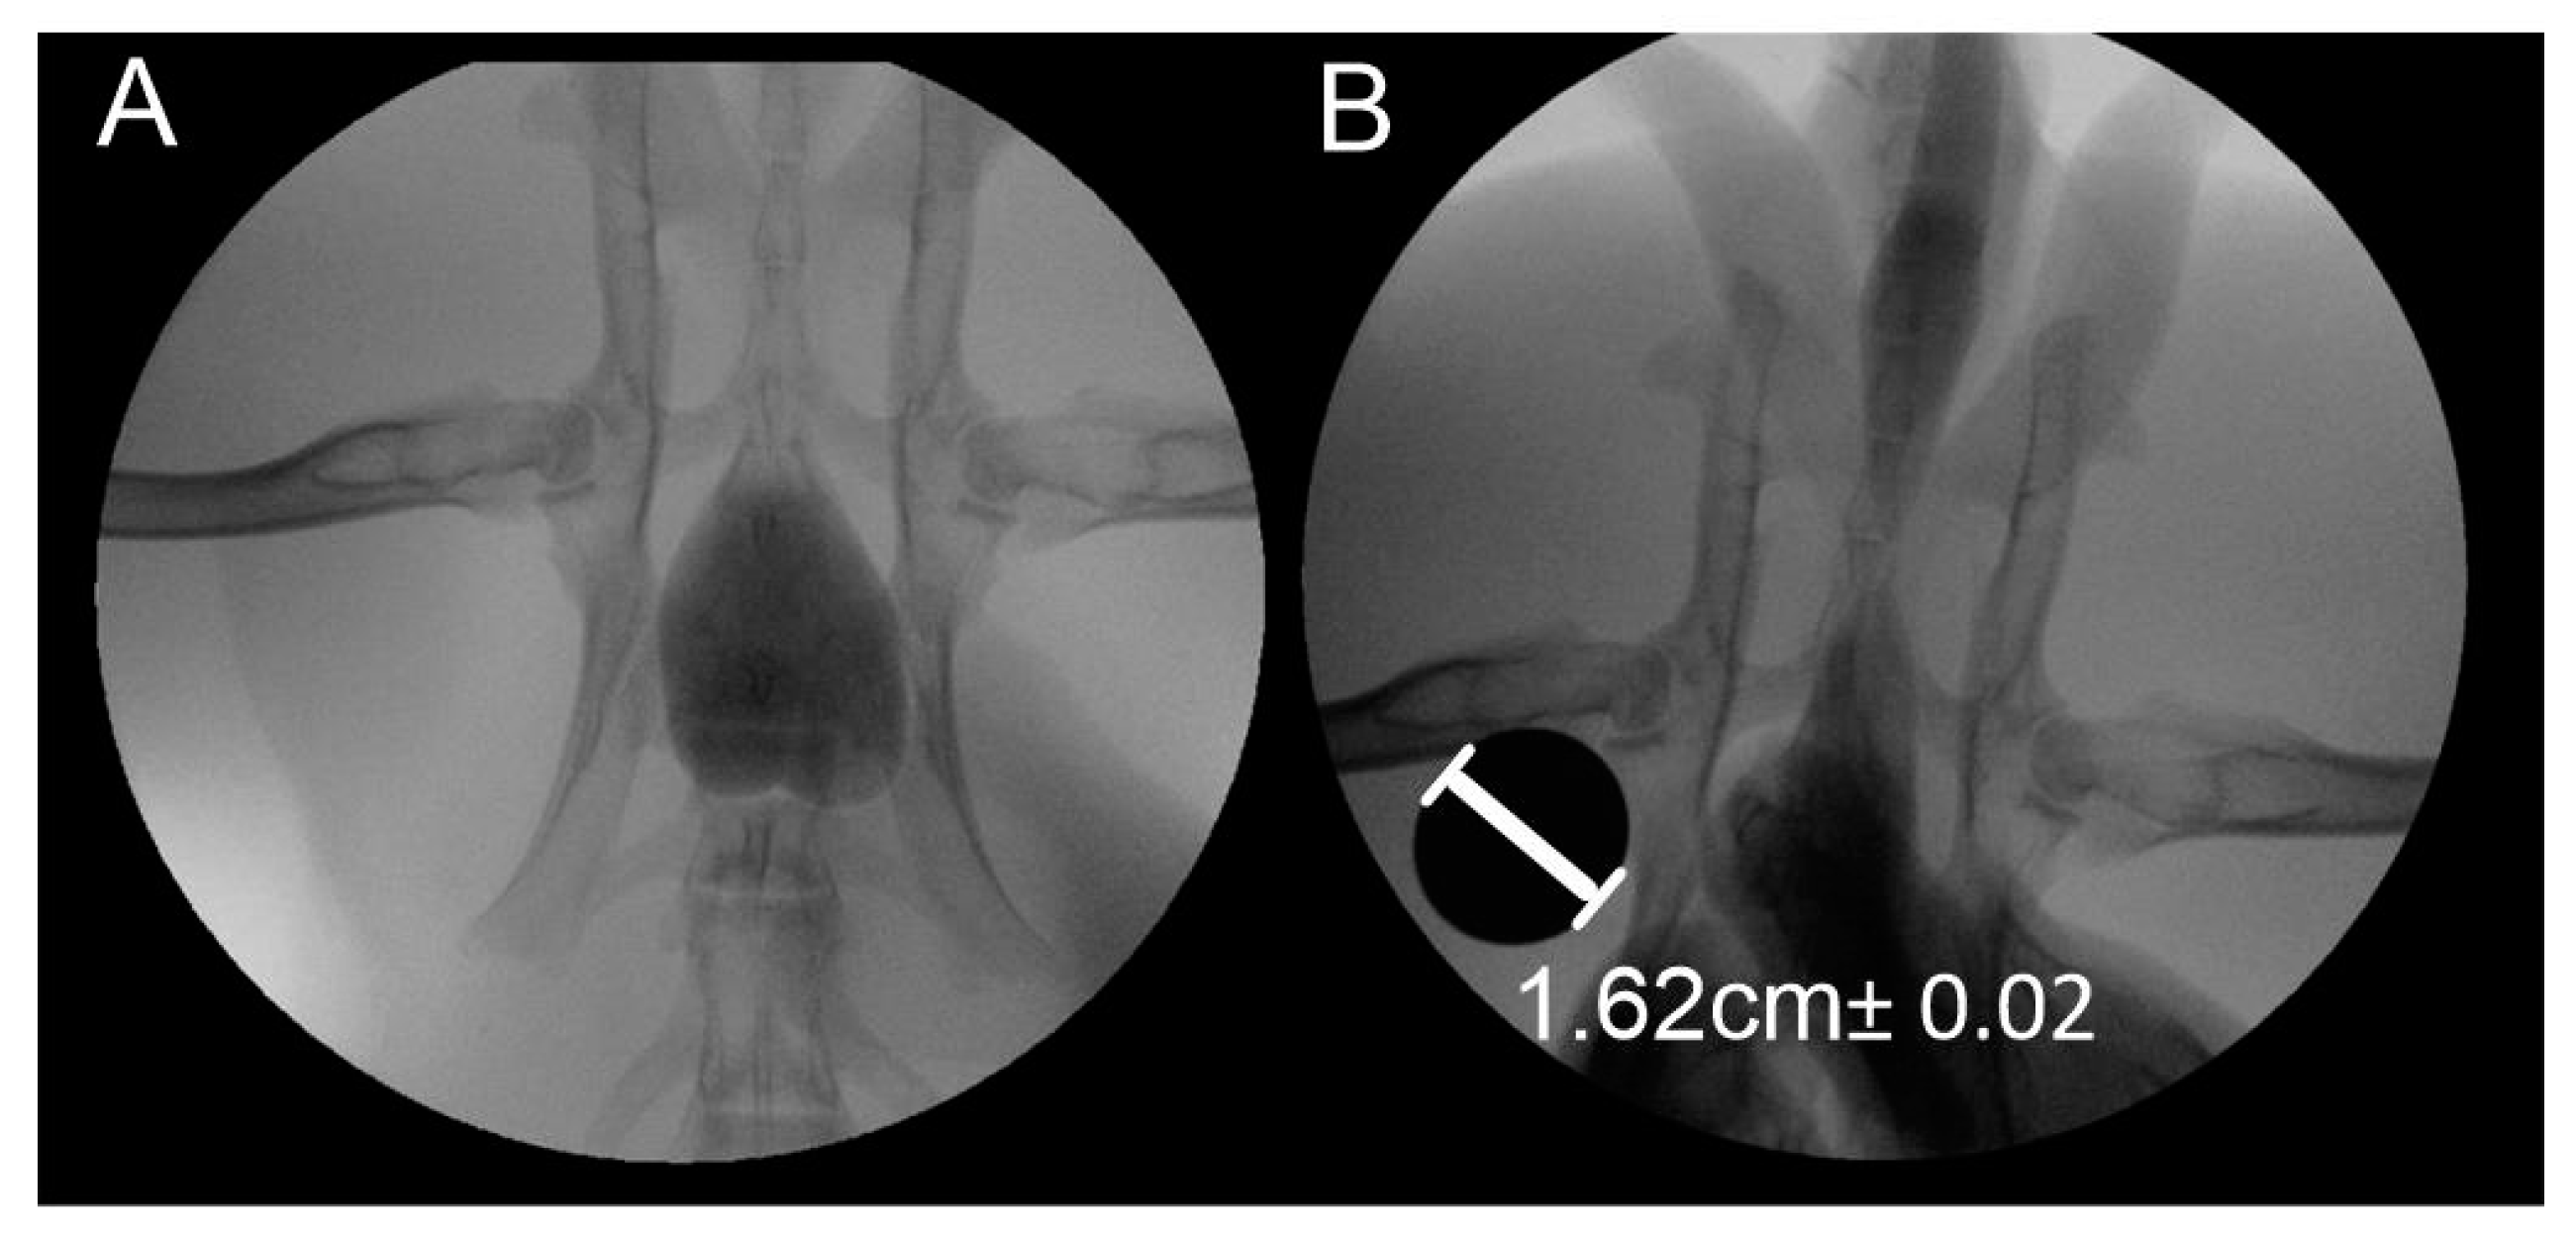

2. Materials and Methods

3. Results